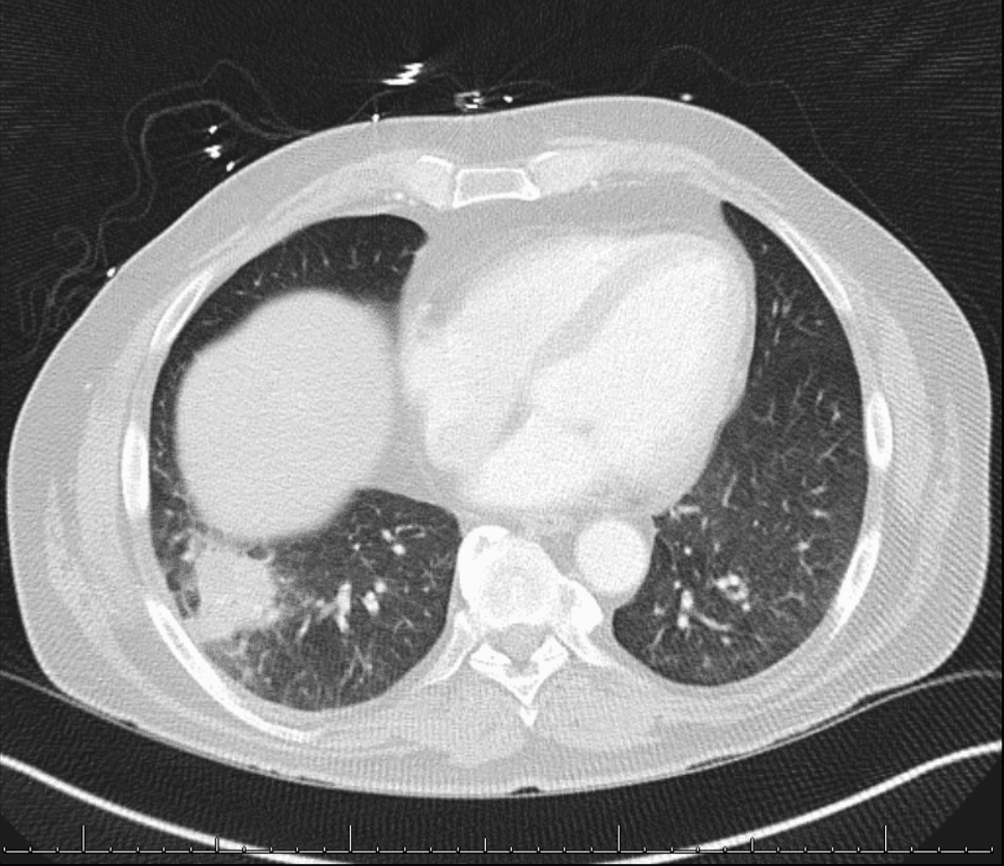

Tests Performed: Fungal biomarkers (negative), blood cultures (negative), sputum and urine mycobacterial cultures (negative), and QuantiFERON-TB Gold test (positive). CT scans of sinuses, chest, abdomen, and pelvis showed improved typhlitis and calcified hilar lymph nodes with scattered 2-3 mm nodules on chest CT.